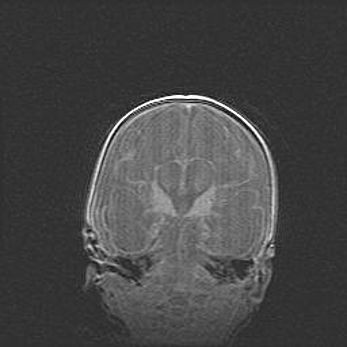

Открытая гидроцефалия.

Возраст: 6 месяцев 15 дней

Вес: 6200 г

Пол: женский

Окружность головы: 41 см

Срок гестации: 38 недель

Гидроцефалия головного мозга у новорожденных – это скопление избыточного количества цереброспинальной жидкости в головном мозге. Ее избыточное скопление в мозге приводит к патологическому расширению желудочков мозга (четырех полостей, расположенных в глубине белого вещества мозга, заполненных цереброспинальной жидкостью и связанных узкими проходами).

Открытый тип гидроцефалии (сообщающаяся) наблюдается тогда, когда нарушен механизм всасывания ликвора в системный кровоток. При этом типе причиной заболевания чаще всего является перенесенные ранее инфекции (например: менингит),  либо же наличие крови в субарахноидальном пространстве.